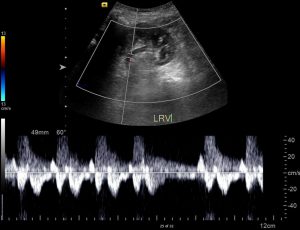

Renal vein thrombosis should be suspected in patients with flank pain and hematuria, especially if accompanied by impaired renal function. The best imaging studies to make the diagnosis are computed tomography (as seen above) or magnetic resonance imaging. On imaging a filling defect will be seen within the renal vein. The filling defect may extend into the inferior vena cava. The kidney itself may show a renal cell carcinoma or edema from congestion. Theoretically renal duplex ultrasound will show lack of flow within the renal vein, however this is not a reliable test for this diagnosis. If you cannot identify normal flow, but you still suspect the diagnosis, you should opt for another imaging modality.